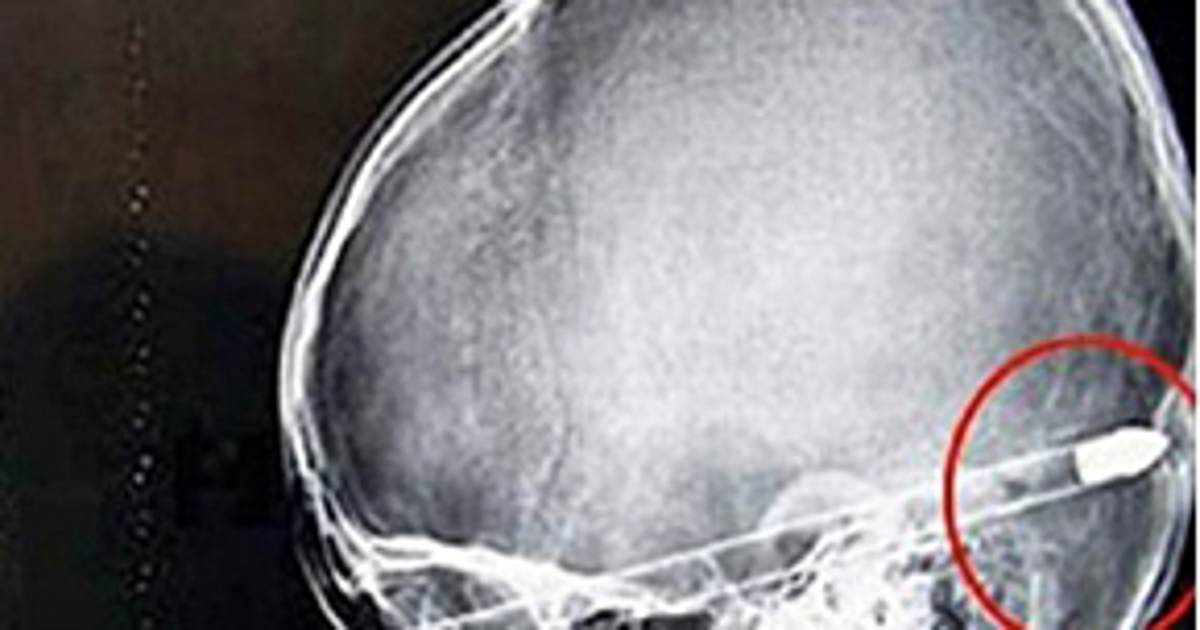

El disparo que recibió el delantero Salvador Cabañas dejó una bala alojada en el lóbulo frontal izquierdo de su cerebro, y de acuerdo con especialistas, el que se quede ahí no generará mayores problemas, sin embargo los daños y secuelas que se podrían presentar dependerá de la trayectoria del proyectil.

El lóbulo frontal es una región del cerebro que se encarga de funciones asociadas a la capacidad intelectual y las habilidades motoras aprendidas, el delantero azulcrema podría, en un inicio, caminar con torpeza por algún tiempo, aunque la rehabilitación ayuda a sanar las zonas dañadas.

De acuerdo con Luna hasta un año mínimo de rehabilitación es lo indicado para saber cómo quedarán las habilidades psicomotoras del paciente.

"Si la lesión es hacia el lóbulo posterior se puede afectar la zona de la corteza que controla los movimientos del lado derecho del cuerpo. Llegando a parálisis de extremidades".

Si la lesión es hacia la parte frontal los problemas se dirigen a la memoria de corto plazo y habilidades intelectuales como operaciones matemáticas simples.